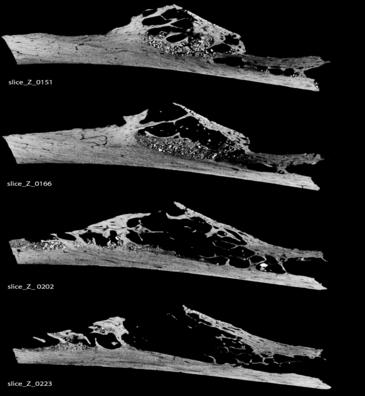

| La costilla cancerosa fue recuperada en la famosa excavación arqueológica de la ciudad croata de Krapina. / Penn Museum |

Los autores destacan que la costilla cancerosa, recuperada en la famosa excavación arqueológica de la ciudad croata de Krapina, es una muestra incompleta, por lo que no pudieron definir los efectos en la salud que dicho tumor podría haber tenido sobre este individuo.